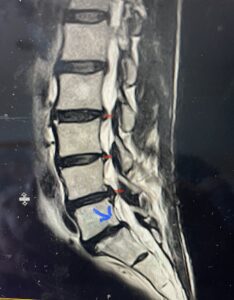

(Fig 1) Hydroxyapatite Coated Pedicle Screw

Pedicle screws can be coated with a thin layer of hydroxyapatite (Fig. 1), which is a natural form of calcium apatite present in human bone and plays a role in the structural strength of bone and in bone regeneration. By coating the screws with hydroxyapatite this can improve screw fixation or bonding at the bone-implant interface